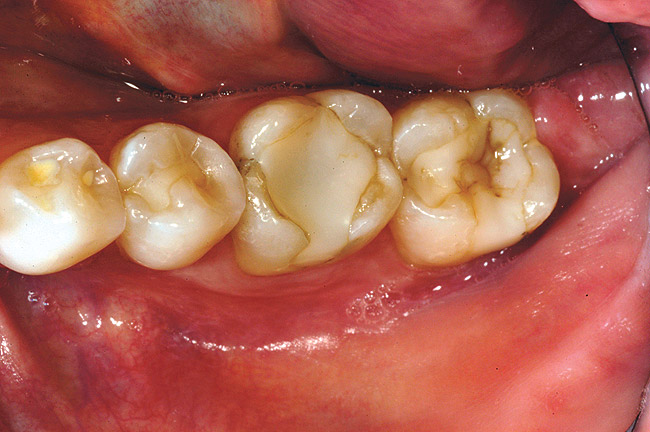

While in vitro studies do not definitively demonstrate a correlation between fracture resistance and cuspal coverage, cuspal coverage is still considered important in instances where the remaining tooth structure is less than one third to one half of the intercuspal distance.22,23 Other factors that support cuspal coverage of posterior teeth are the position of the tooth within the arch, with molars subject to greater bite forces and, therefore, exhibiting a greater need for cuspal coverage.24,25 Cracked teeth also warrant cuspal coverage (Figure 1A through Figure 1C).26,27

Figure 1a  A patient presents with large direct composite restorations and multiple crack lines in teeth Nos. 18 and 19. Tooth No. 19 was symptomatic to biting pressure.

Figure 1a

Figure 1b  The teeth were prepared for adhesively retained restorations. Note the significant ring of remaining enamel.

Figure 1b

Figure 1c  The final restorations restore and protect the compromised cusps.

Figure 1c